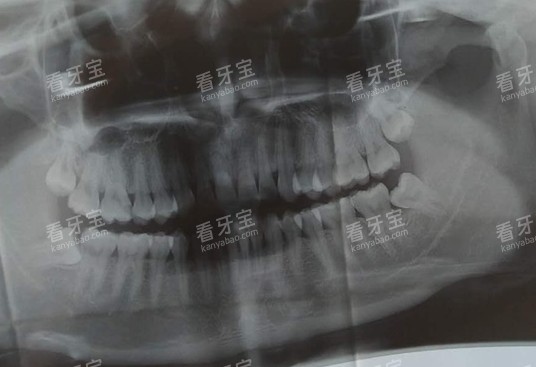

3.重视检查与方案:规范的机构一定会先拍X光片(小牙片或全景片),看清蛀牙的深度、范围、与牙髓的关系。不拍片就直接补的,要谨慎。